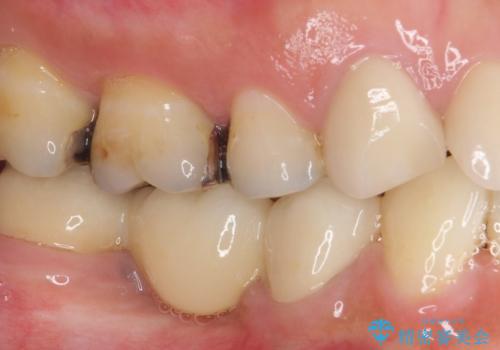

- 奥歯に痛みを感じるようになり、更にはその前の歯のセラミックが欠けてしまったとのことで来院された患者様です。

痛みがしばらく続いていたため、抜髄となる可能性を考慮しながら処置を行うこととしました。

処置後に痛みの状態を確認し、前歯のクラウンの再製作を同時に進めることとしました。

銀歯の下の虫歯はそれほど大きくなく、初回の処置以降、痛みを感じることはなくなりました。

セラミックインレー装着後も痛みが生じることはなく、神経の状態も正常な反応が認められました。